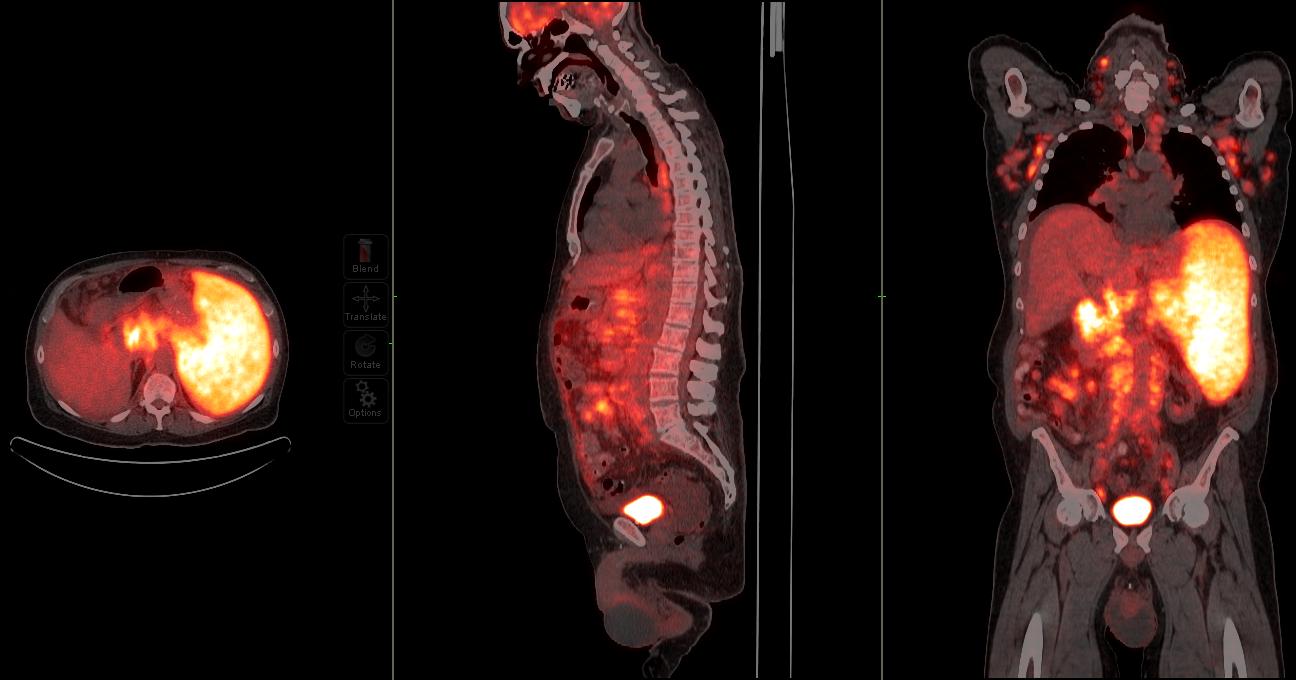

Image: PET/CT scan showing extensive FDG-avid tumor featuring.

PET/CT scan showing extensive FDG-avid tumor featuring